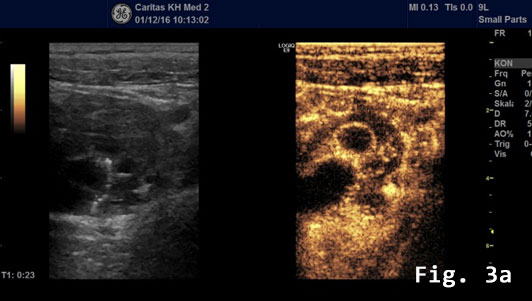

Contrast enhanced ultrasound (CEUS) showed a rapidly and heterogeneously enhancing lesion during the arterial and venous phases [Figure 3]. Contrast enhanced colour Doppler ultra-sound confirmed the finding.